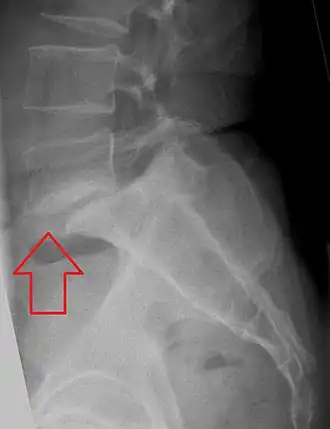

Imagerie

Faire le diagnostic : les clichés standard peuvent montrer la lyse à un œil entraîné, les clichés centrés de 3/4 font toujours partie de l'arsenal diagnostic à la recherche de la décapitation du petit chien radiologique de Lachapelle [7, 76]. Les coupes de scanner peuvent aider [114] mais peuvent aussi passer dans le plan de la lyse et être difficiles à interpréter, quelquefois ce sont seulement les reconstructions tridimensionnelles dans le plan des isthmes qui permettent de trancher [45]. Dans certaines formes infra radiologiques en particulier chez le jeune sportif lombalgique, la scintigraphie osseuse au Tc 99 peut faire suspecter la lyse en montrant une fixation uni ou bilatérale [54]. La scintigraphie permet également de suspecter le caractère récent d’une lyse constituée chez un patient jeune [43, 117]. Le diagnostic précoce a un intérêt si on peut par un traitement précoce (diminution des activités, immobilisation) éviter de passer au stade de lyse radiologiquement constituée [52]. Chercher autre chose : chez un adulte lombalgique chronique ou qui se plaint de radiculalgies, la lyse isthmique est l'arbre qui cache la forêt [120] … hernie discale intra ou extra canalaire, au même niveau [94] ou à un autre niveau, tumeurs rachidiennes [8], voire ostéome ostéoïde [85] sont des diagnostics associés possibles, en marge de la lombalgie essentielle d'origine discale pure dont la physiopathologie et les indications thérapeutiques restent discutées [12]. Bilan préthérapeutique : L'IRM montre le volume du “ nodule de Gill ” , une anomalie radiculaire associée, une hernie discale au même niveau (en se méfiant des effets de volume partiel qui sont beaucoup plus fréquents), l'état du disque [31], et celui du disque sus-jacent [59] dans une perspective chirurgicale.

Le cliché de profil montre et quantifie le glissement antérieur du corps vertébral, mais le bord postérieur du sacrum peut être difficile à percevoir. Les 3/4 montrent le plus souvent la lyse isthmique lorsqu’elle existe. Compte tenu de la fréquence des spondylolisthésis de grade I bien tolérés, le bilan complémentaire recherche d’autres pathologies à même d’expliquer une symptomatologie lombaire ou radiculaire chez un adulte jeune [44], en particulier à un autre niveau. Enfin dans une perspective chirurgicale, on recherche l’état d’hydratation du disque sus-jacent, le volume du tissu de pseudarthrose, la morphologie des pédicules et la présence de “ crochets ” pédiculaires nécessitant résection.